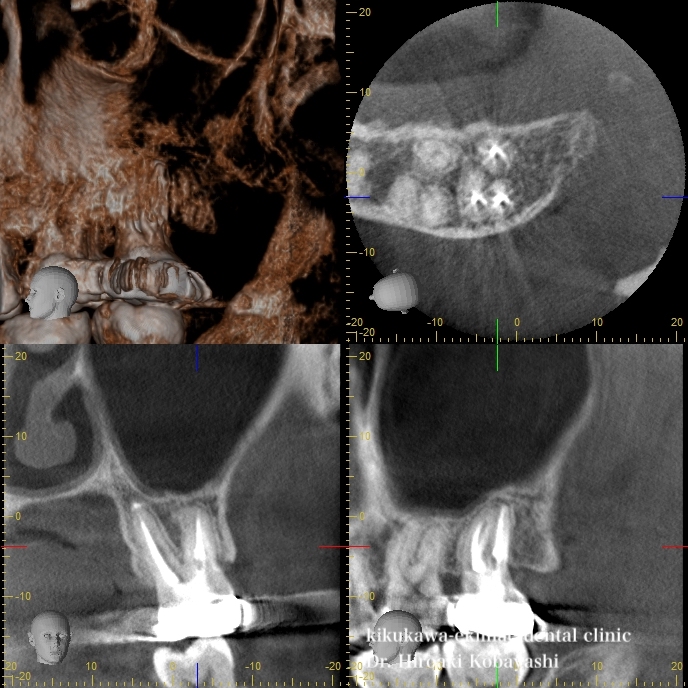

精密根管治療を行う事で歯の中の細菌がいなくなり、骨の再生と上顎洞炎が治りました。

約2時間〜1、5時間程度の根の中の消毒を2~3回程度行う事で歯の中の殺菌を行う事ができます。